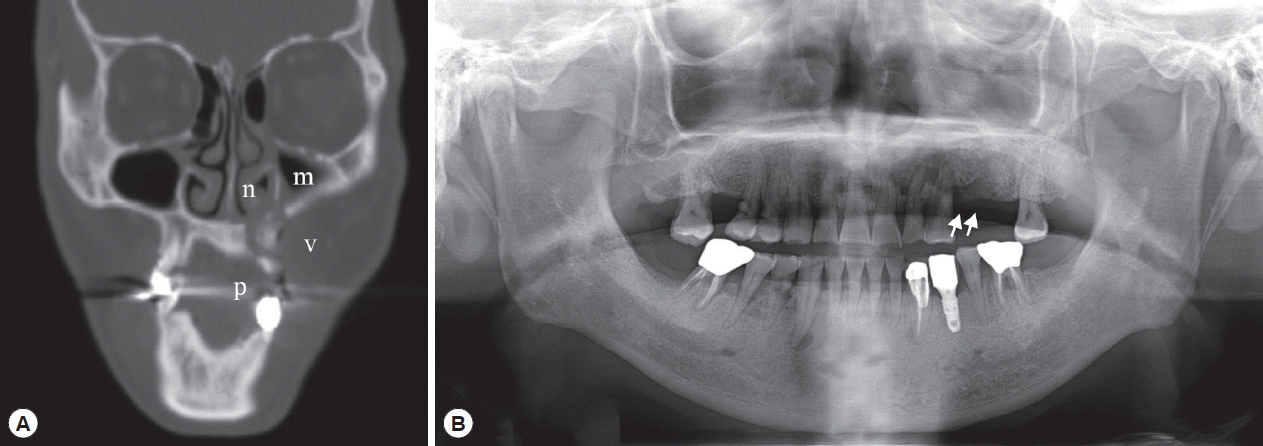

A Case of Pentastomiasis at the Left Maxilla Bone in a Patient with Thyroid Cancer